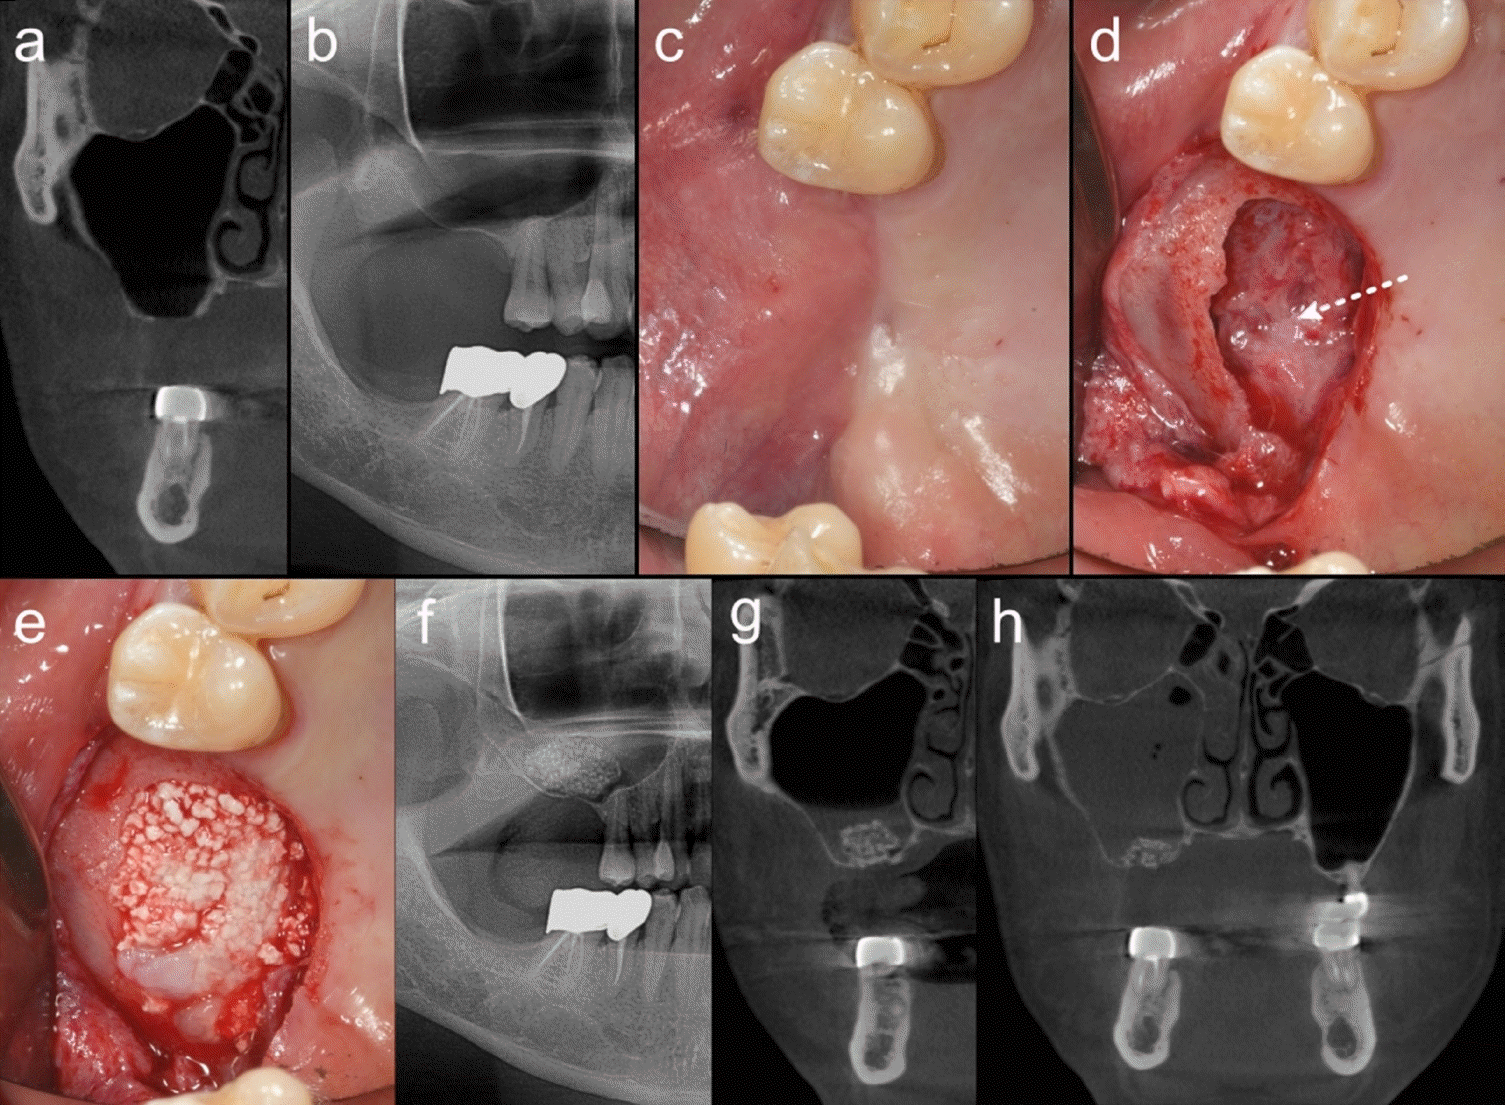

Figure 2.

Clinical and radiological findings at follow-up and during sinus floor augmentation (SFA). a, b. Computed tomography (CT) and panoramic radiograph after treatment of prior sinusitis, showing a fully healed maxillary sinus with an alveolar bone defect. c. Clinical photograph before the SFA procedure, showing well-healed oral mucosa. d. Clinical photograph during the SFA procedure, showing a large bone perforation and regenerated sinus mucosa (white dotted line). e. Sinus mucosa elevated without tearing, and bone graft performed. f. Panoramic radiograph after SFA, showing well-positioned bone graft materials without scattering. g. CT taken after SFA. The air-fluid level suggests minor tearing of the sinus mucosa or congestion of blood/tissue fluid during membrane elevation. h. One-month postoperative follow-up CT showing near complete haziness in the operated maxillary sinus.